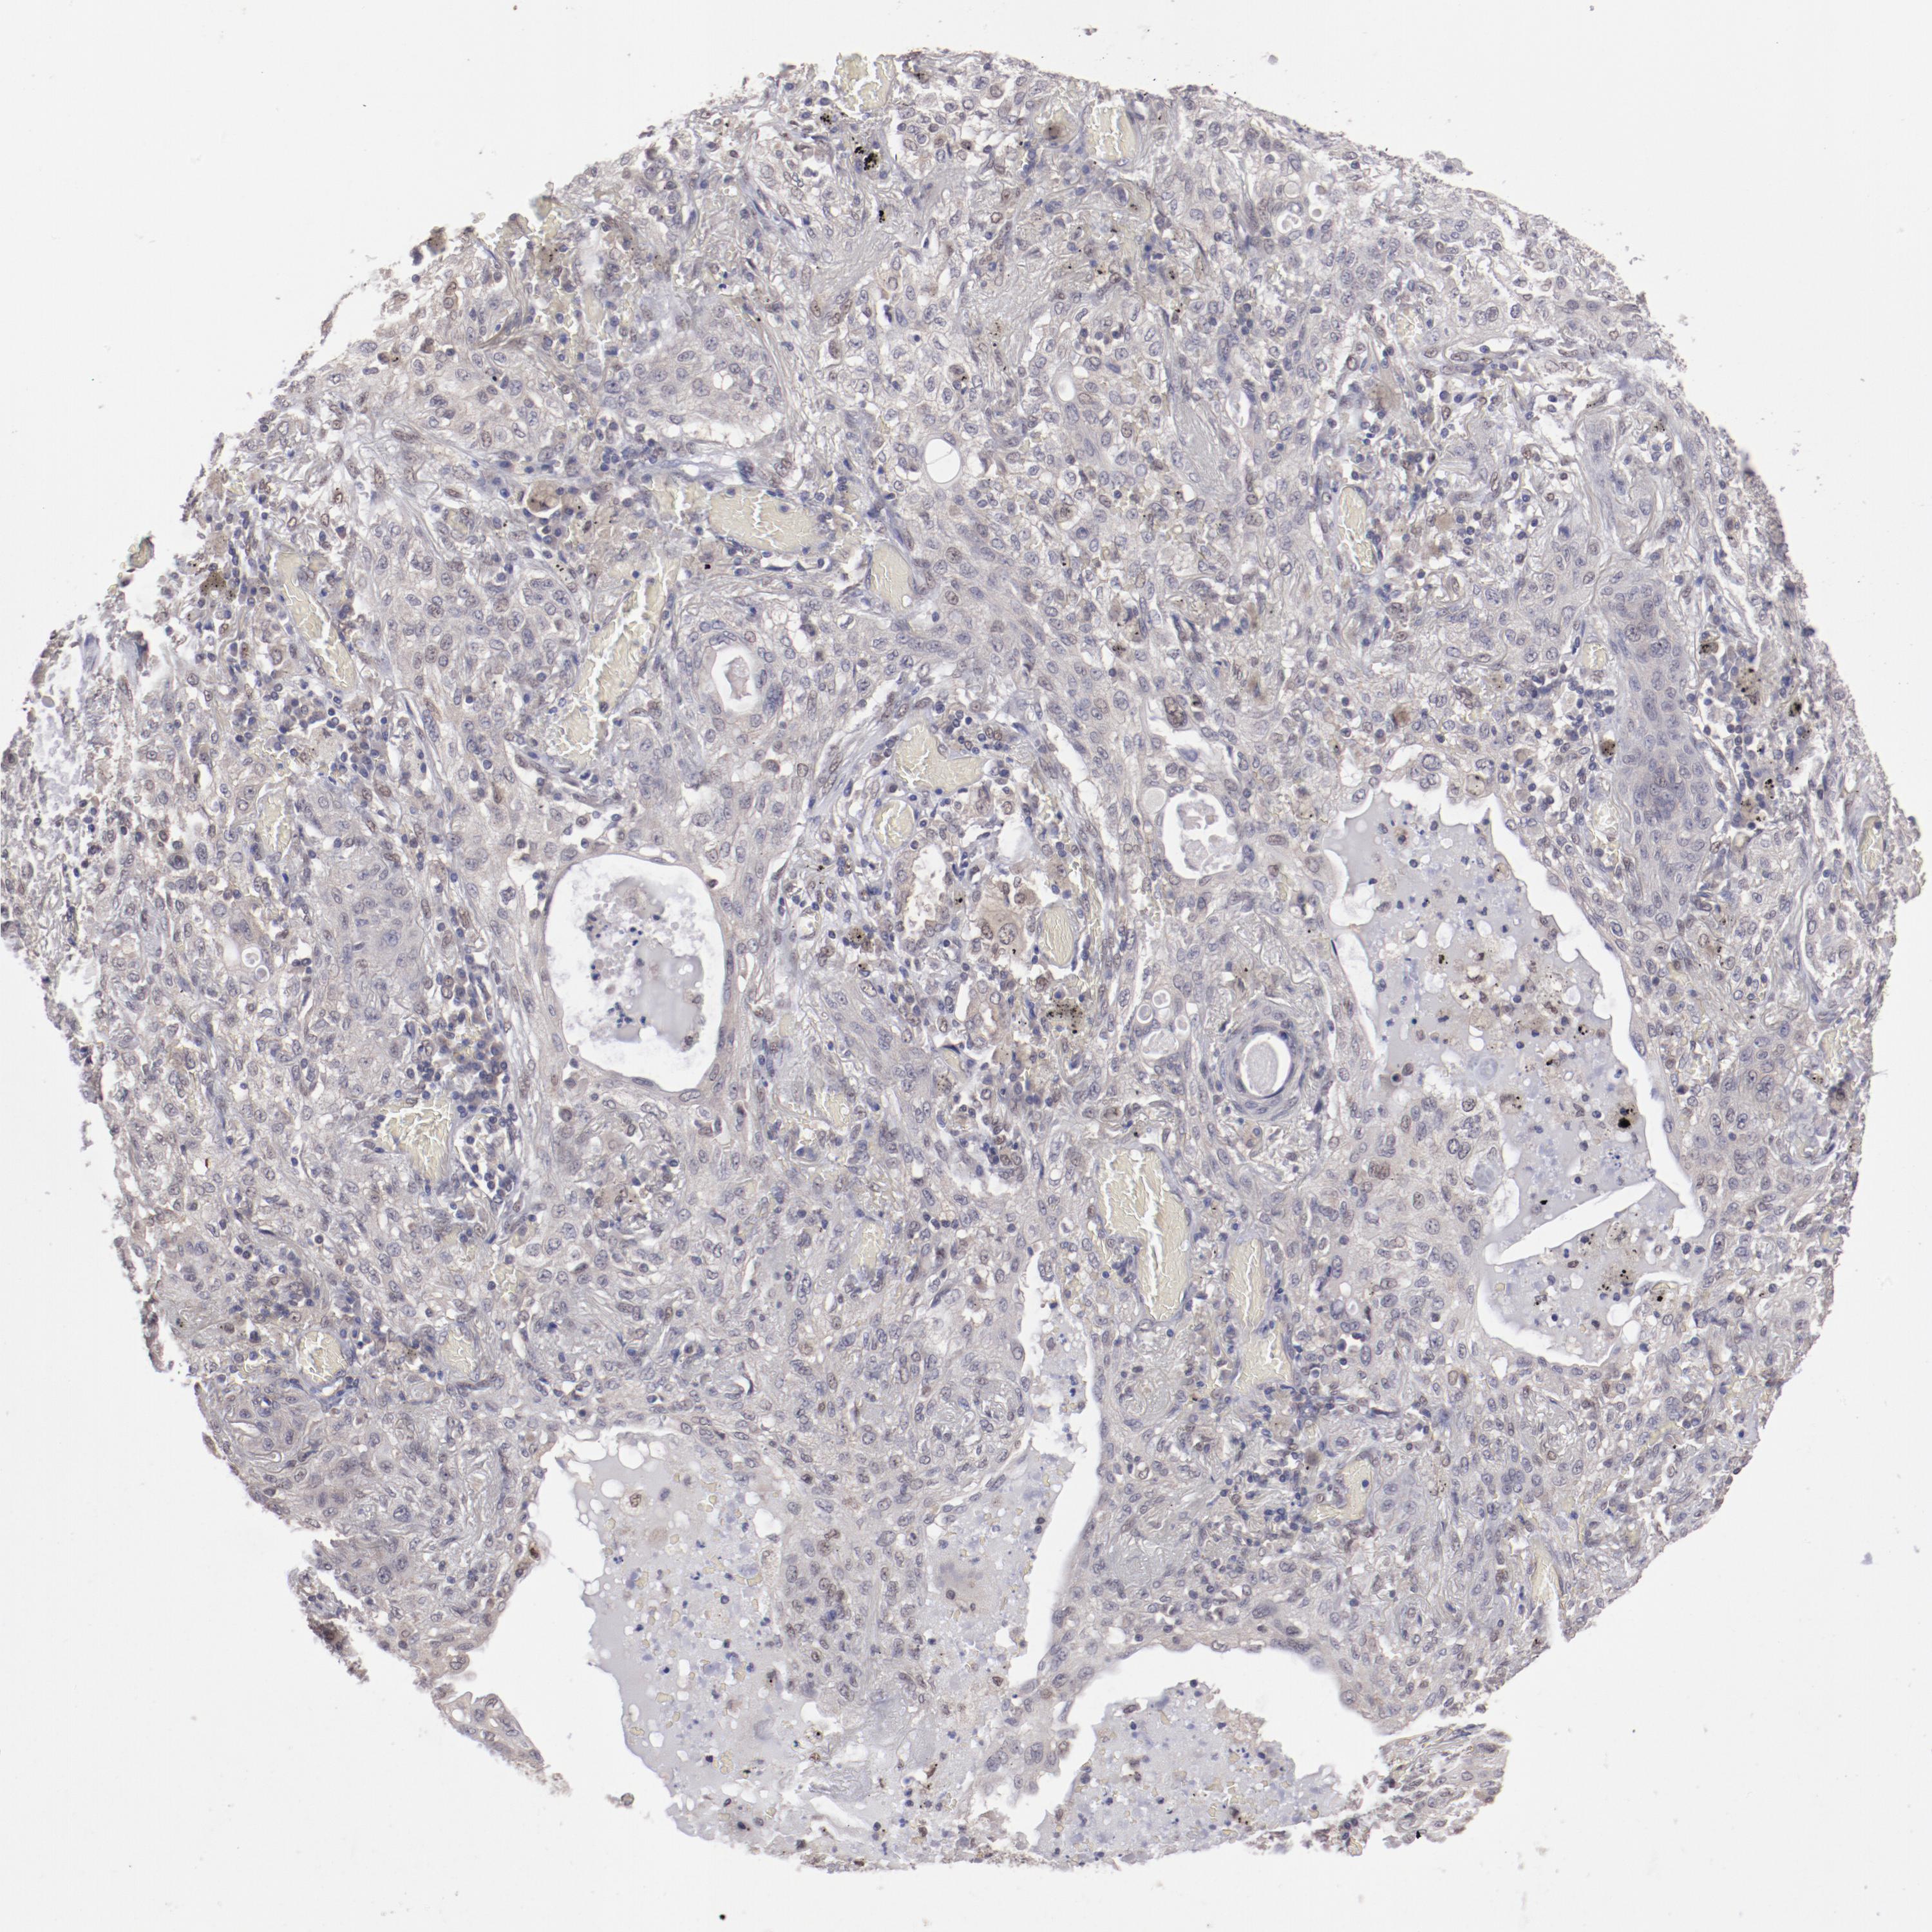

CANCER LUNG CANCER Show tissue menu

LUAD TCGA LUAD VALIDATION LUSC TCGA LUSC VALIDATION PROTEIN LUAD CPTAC PROTEIN LUSC CPTAC PROTEIN EXPRESSION